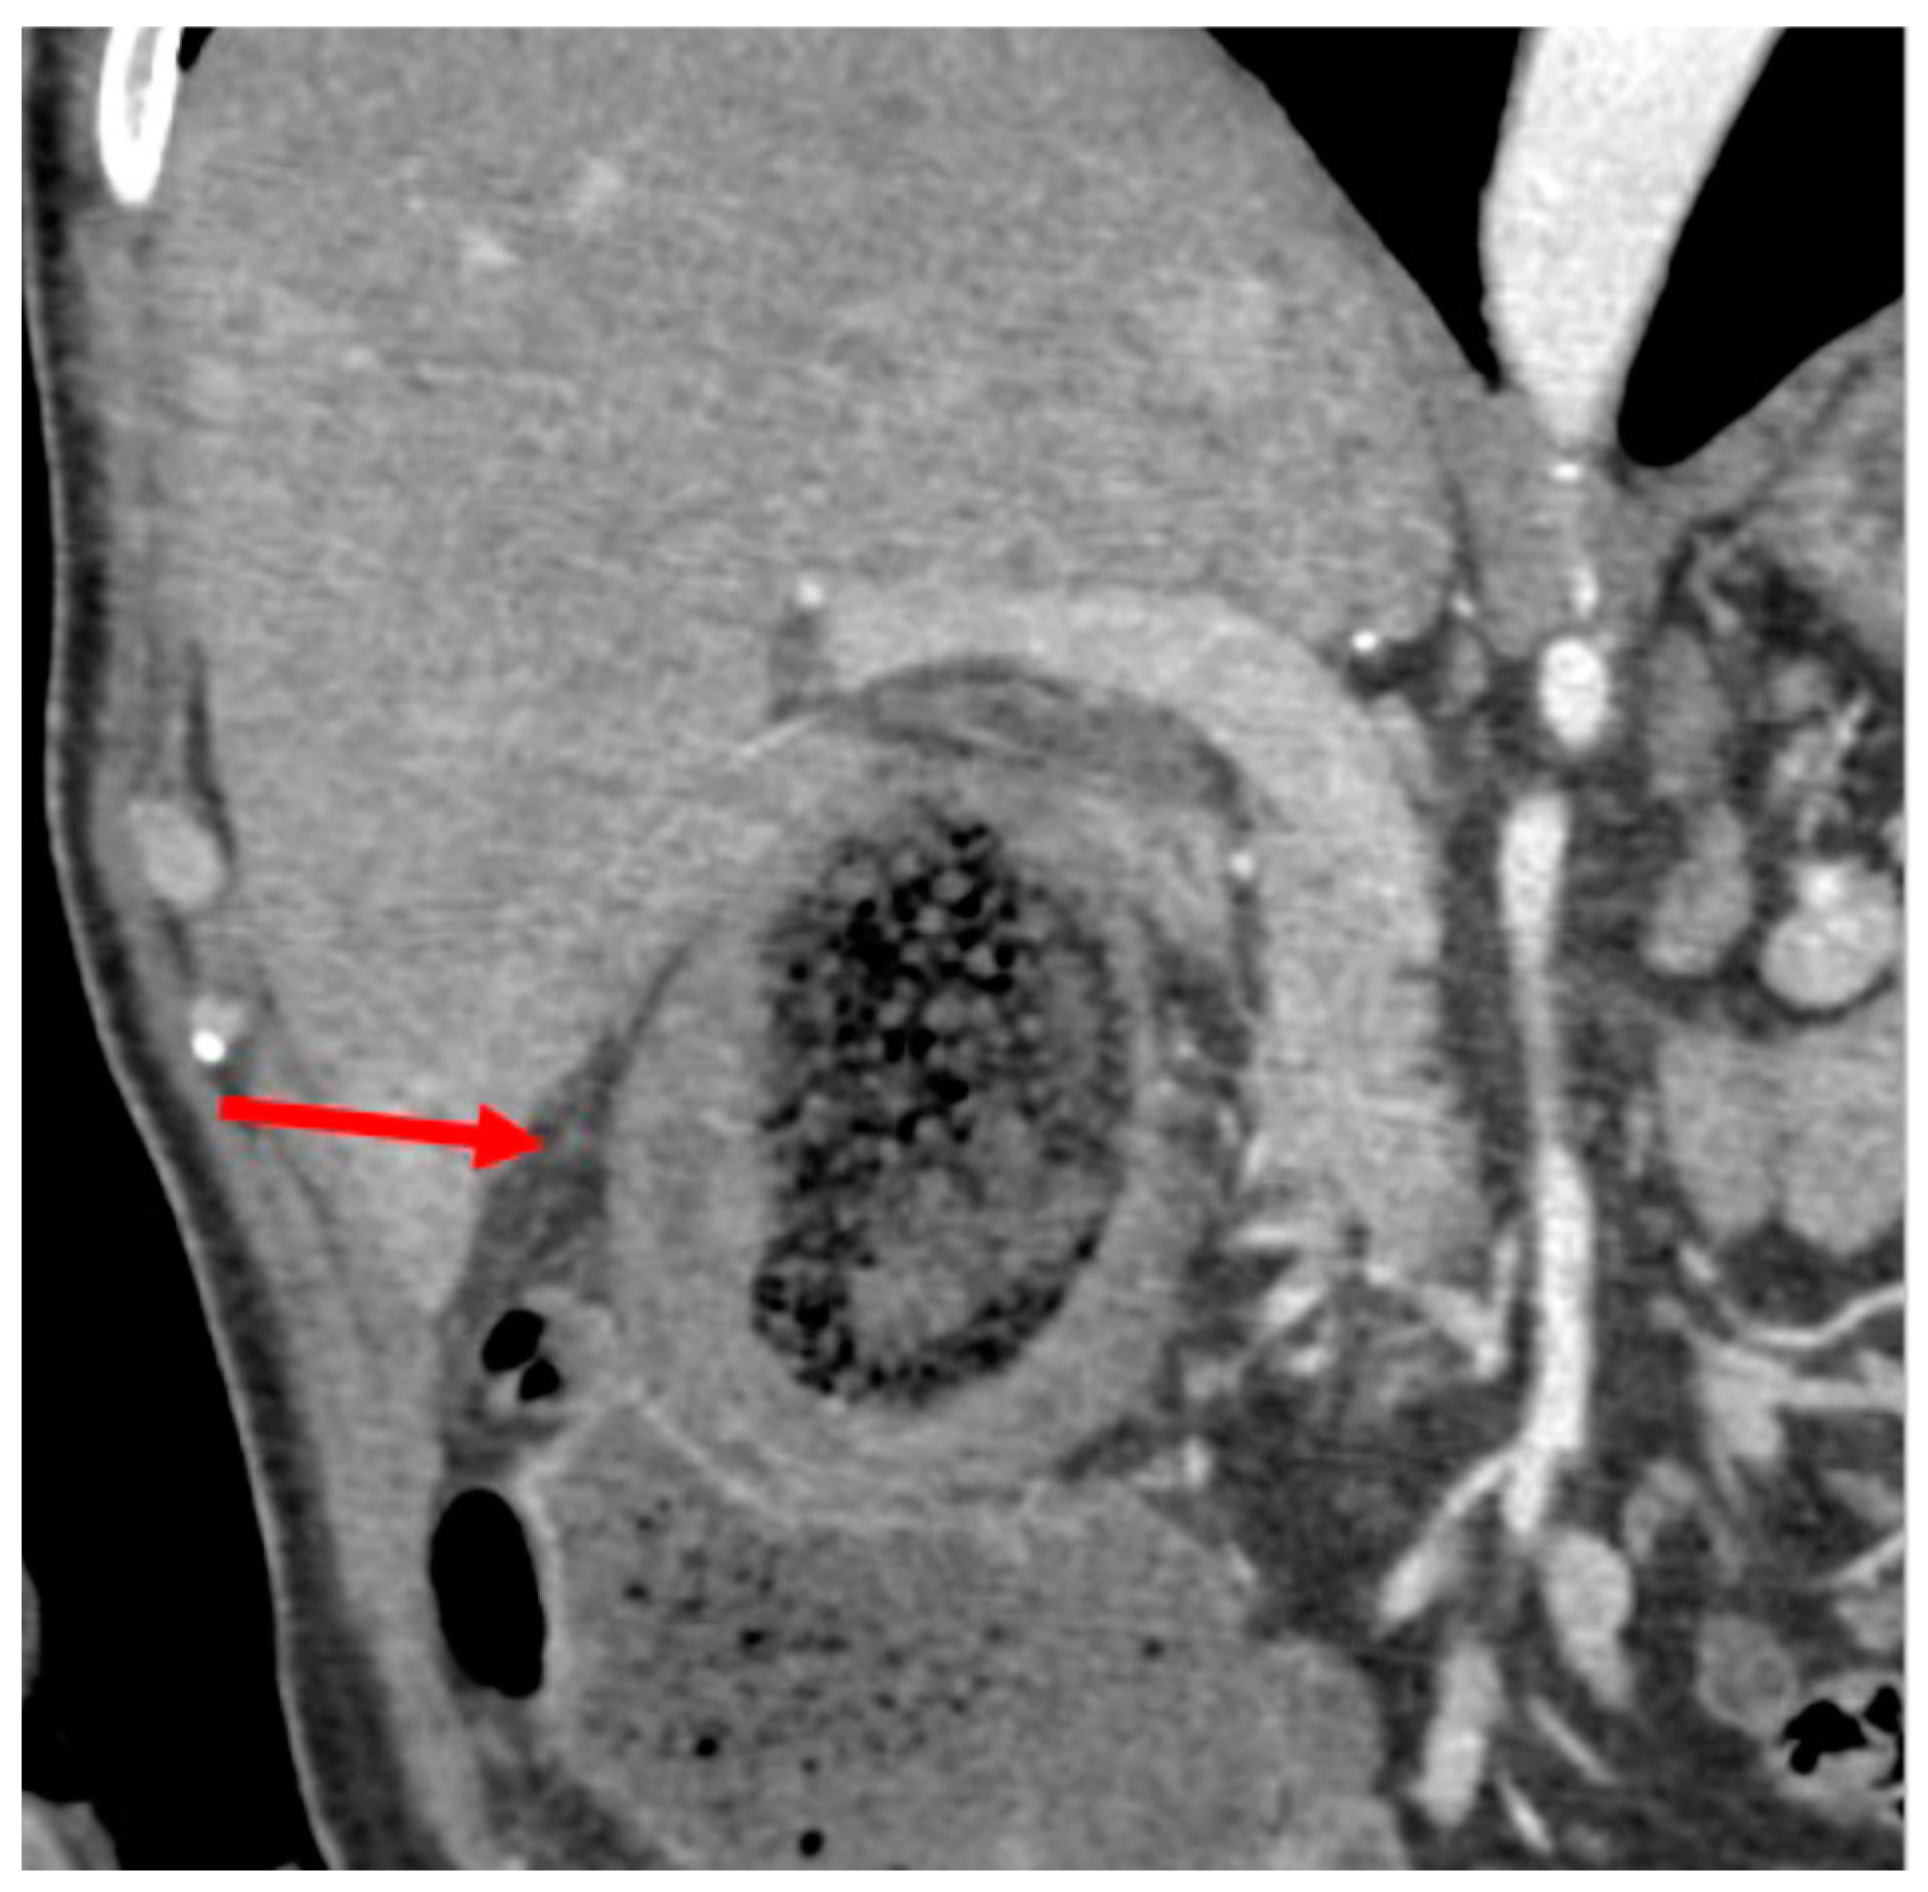

2. Case Report